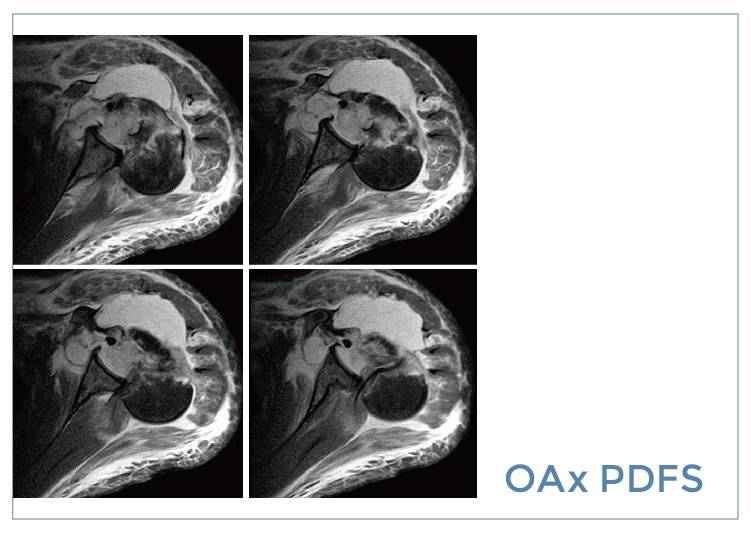

【朗润影像档案】磁共振影像病例分享(编号20190906)